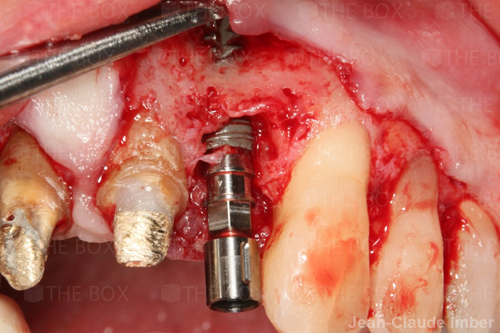

A new case was made public by Jean-Claude Imber check it out here.